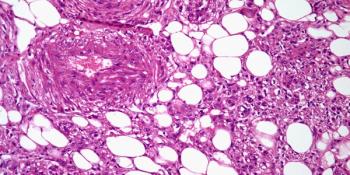

A 52-year-old woman presents with a right kidney mass. What is your diagnosis?